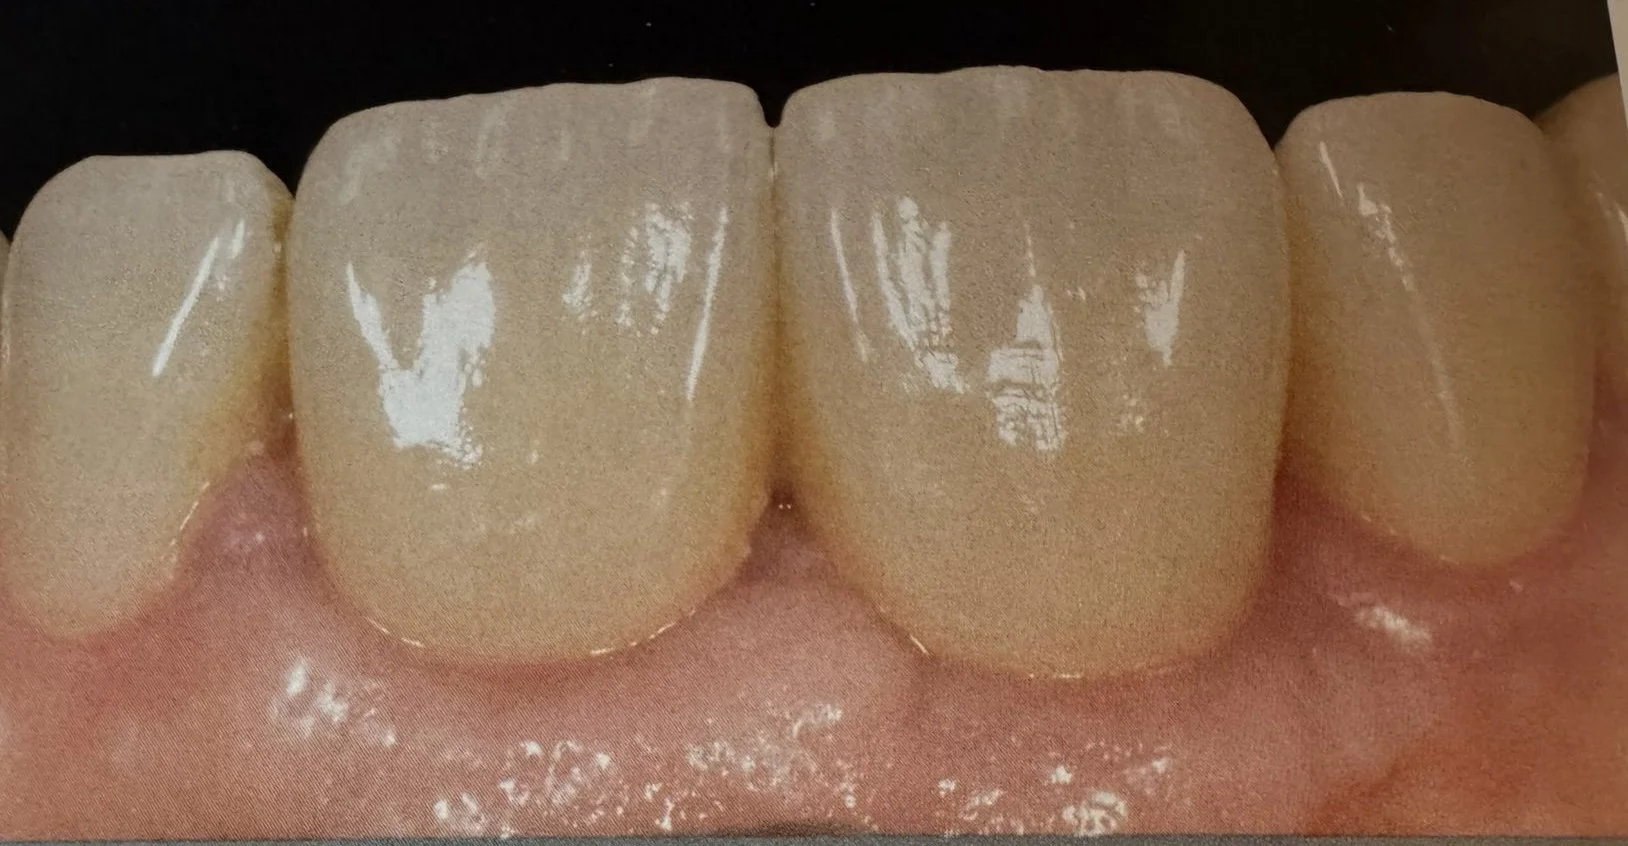

Ricostruzione dei colletti